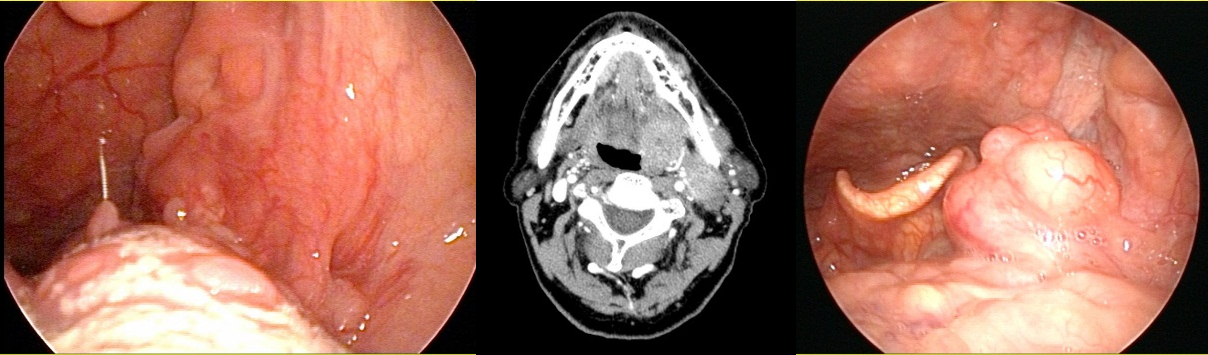

두경부암의 진단의 경우에는 크게 신체검사와 영상검사를 통해서 진단하게 됩니다. 신체검사의 기본은 이비인후과적 내시경 검사이며 이때 환자가 호소하는 증상과 연관된 부위를 중심으로 증상을 유발할 수 있는 모든 부위를 내시경으로 자세히 검사하게 됩니다. 두경부암의 경우 경부임파선 전이가 드물지 않기 때문에 양손을 이용하여 전문의가 시행하는 경부 촉진검사 또한 매우 중요합니다. 원발부위로 의심되는 병변이 발견될 경우에는 접근이 쉬운 부위의 경우 외래에서 조직검사를 바로 시행하며, 후두암이나 하인두암 같이 외래에서 조직검사가 용이하지 않은 부위는 조직검사 및 병변의 진행정도 평가를 위해서 전신마취를 해야 할 수 있습니다. 또한 경부전이 여부를 정밀검사 하기 위하여 경부 전산화단층 촬영(CT) 및 초음파 검사를 시행하게 됩니다. 마지막으로 진행된 두경부암의 경우에는 최종 치료 방침을 결정하고 치료를 시작하기 전에 원격전이가 없는지 여부 확인을 위해서 PET 검사를 추가로 시행하게 됩니다.

구강암: 설암, 구강저암, 입술암

구인두암: 편도선암, 경부임파선 전이가 있는 편도선 암, 혀뿌리암

하인두암, 성문상부 후두암, 성문부 후두암

비부비동암: 상악동암, 비강암

침샘암 (이하선암), 기도와 식도를 침범한, 다수의 경부임파선 전이를 동반한 진행된 갑상선암